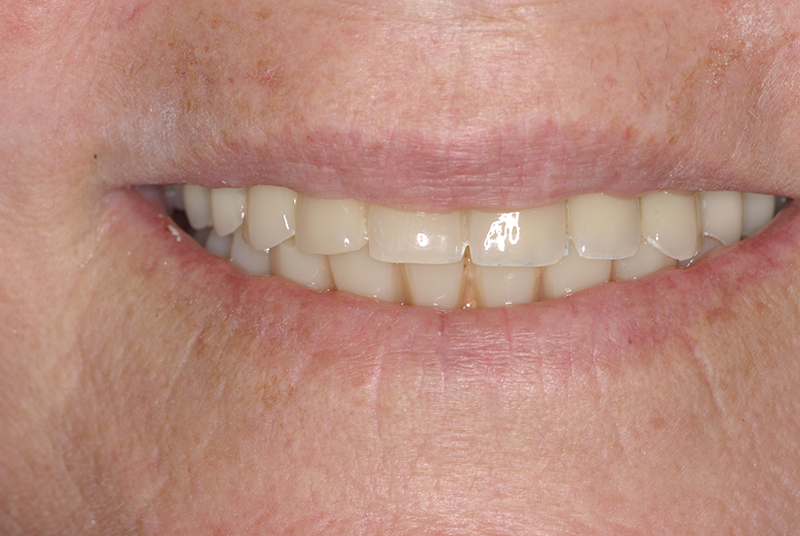

- Conforto e Estética: A prótese provisória é funcional e visualmente semelhante aos dentes naturais.

- Melhora da autoestima: O impacto positivo de um sorriso completo é imediato, melhorando a qualidade de vida.